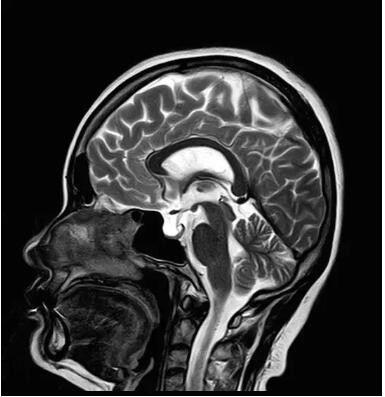

佳能磁共振推出了全新一代Vantage Elan1.5T磁共振,這款日本原裝進(jìn)口的 1.5T磁共振,集當(dāng)今磁共振創(chuàng)新科技成果于一身:

Pure 射頻影像鏈——圖像信噪比提升40%

眾所周知,磁共振成像最核心的三個(gè)部分:磁體、梯度、射頻,此三部分為磁共振成像之魂,直接決定著磁共振成像的圖像質(zhì)量--圖像信噪比。各個(gè)廠家在磁共振成像提升圖像信噪比的道路上不斷探索和創(chuàng)新,致力于信噪比的提升,各個(gè)廠家側(cè)重點(diǎn)不同,在各自領(lǐng)域各有所長(zhǎng),在本世紀(jì)第二個(gè)十年,各個(gè)廠家都在做不同的嘗試和改進(jìn),例如:A廠家的“太空艙”技術(shù),旨在解決射頻發(fā)射和射頻接收的實(shí)時(shí)互補(bǔ)……;B廠家的ADC前置所謂的“全數(shù)字”技術(shù),旨在解決信號(hào)模數(shù)轉(zhuǎn)換的時(shí)間早晚……;C廠家的“光纖”技術(shù),旨在解決信號(hào)傳輸路徑的信號(hào)損失……;各家都在一定程度上解決了信號(hào)的損失,信噪比在一定程度上有所提升,但是并未從根本上解決信噪比大幅度提升。

佳能公司在2018年率先提出了Pure射頻成技術(shù),從源頭上解決信噪比的提升,著眼于全路徑、全成像鏈的優(yōu)化和改進(jìn)。

3.Pure射頻成像鏈

從成像源頭的磁體采用鍍膜新磁體高密度薄層鍍膜貼合技術(shù),獲得更好的磁場(chǎng)均勻度,奠定磁共振成像基礎(chǔ);采用3D RSCE微雕梯度精準(zhǔn)控制頻率和相位,輸出理想波形,實(shí)現(xiàn)渦流的“0”殘余,還原最真實(shí)的圖像信息;射頻接收端通過(guò)計(jì)算機(jī)人工智能對(duì)信號(hào)抗干擾處理,把信號(hào)放大并去除梯度、磁場(chǎng)等對(duì)信號(hào)干擾,再經(jīng)過(guò)二次人工智能信號(hào)識(shí)別,去除噪聲污染獲得純凈的信號(hào);通過(guò)Pure射頻成像鏈的優(yōu)化和改進(jìn)使信噪比提升40%,這是磁共振領(lǐng)域革命性的顛覆和改變。